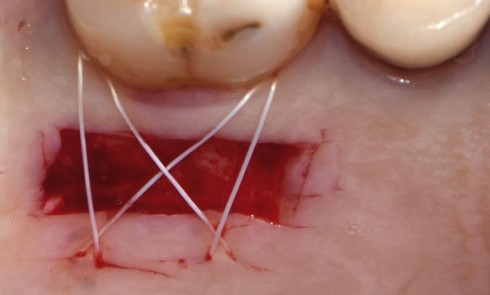

Article réservé à nos abonnés La régénération dans le traitement des défauts infraosseux en 2018

Au fil du temps, différentes techniques chirurgi­cales ont été proposées pour reconstruire les tissus parodontaux en présence de défauts infra­osseux,...